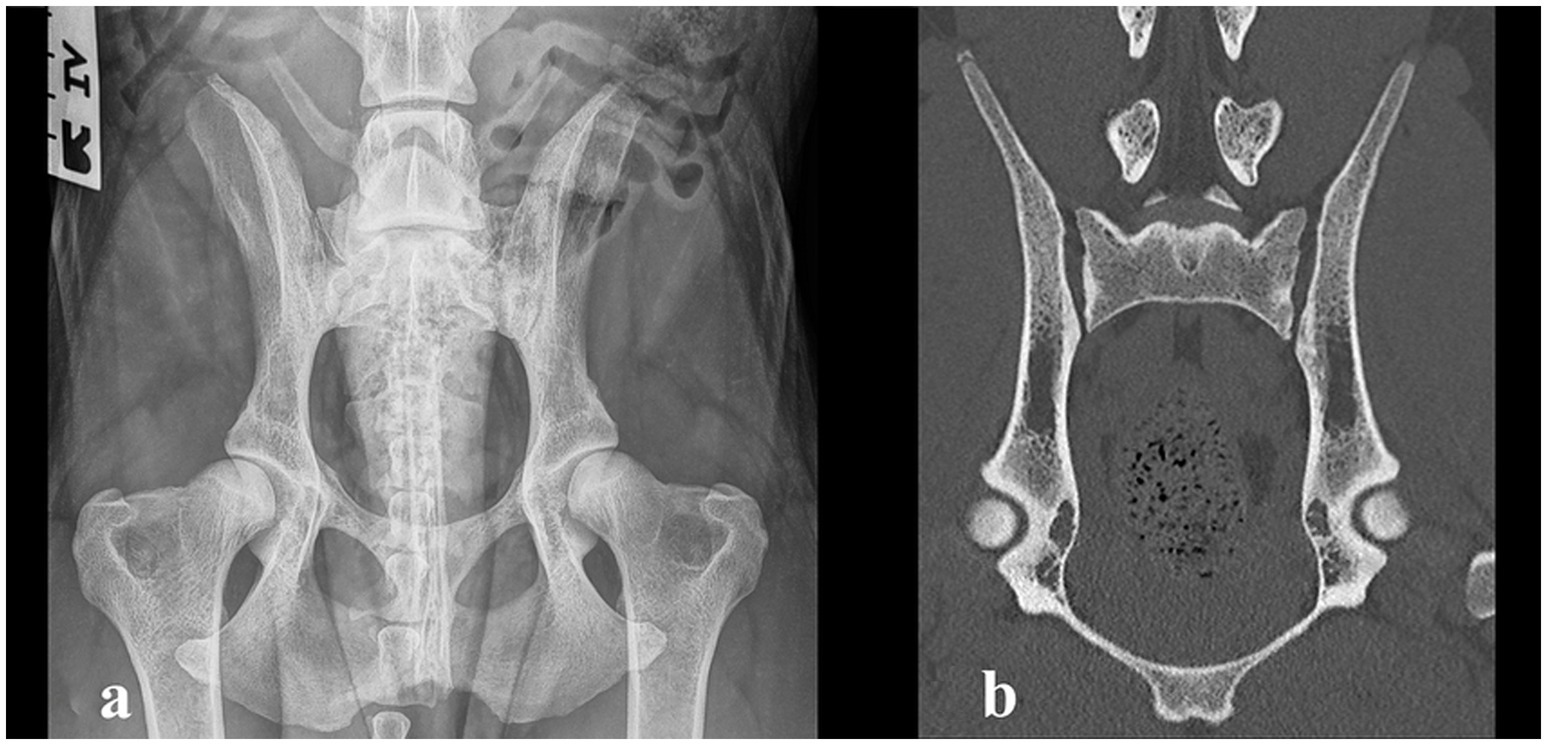

Physiotherapy was continued, and the dog was allowed to return to normal activity. After 1.5 years, the owner reported that the dog maintained normal activity without clinical complaints. Recheck radiography and CT were performed during the official hip and elbow dysplasia screening. Palpation of the SIJs and lumbosacral region was non-painful. The range of motion of the hips was normal and non-painful. Mild tarsal outward rotation was observed clinically, but the orthopedic examination was otherwise unremarkable. The radiographic and CT images revealed no evidence of erosive or sclerotic lesions, and the appearance of the SIJs was considered within normal limits (Figure 3). In the official Fédération Cynologique Internationale hip dysplasia screening, the hips were classified as D/D (moderate hip dysplasia).

Figure 3. (a) Ventrodorsal radiograph taken 1.5 years after the diagnosis, showing complete resolution of the erosive changes in the sacroiliac joint and moderate hip dysplasia. (b) Computed tomography image (coronal plane) of the sacroiliac joint 1.5 years after the diagnosis, showing complete resolution of the changes.